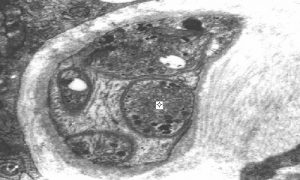

Priečny rez kapilárou. Bunka cievnej výstelky (E). Zväčšenie 21 000-krát.

Tepny a žily vyšších živočíchov majú podobnú štruktúru. Skladajú sa z troch vrstiev navzájom oddelených elastickou membránou: vnútornej, strednej a vonkajšej. Vlásočnice tvorí len jedna vrstva endotelových buniek. To sú bunky, ktoré lemujú celý cievny systém, od srdca až k najmenším kapiláram. Cievy dokážu meniť tlak krvi v systéme aktivitou strednej vrstvy cievnej steny – hladkosvalovými bunkami. Tie sú schopné podľa prichádzajúcich podnetov z vnútornej a vonkajšej vrstvy meniť svoju dĺžku (rozťahovať sa a sťahovať), a tým meniť priesvit a tlak v cieve. Následkom je zmena zásobovania jednotlivých orgánov krvou podľa ich momentálnej potreby. Napríklad po jedle prednostne zásobujú krvou tráviacu sústavu, pri behu zase svaly atď.